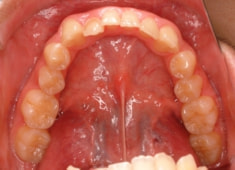

治療前

解説:残存している左上乳犬歯Cを抜歯し、そのスペースに左上3番を誘導しました。Cと犬歯ではスペースが足りないので、前歯をアドバンスさせ、反対咬合を同時に解消しております。